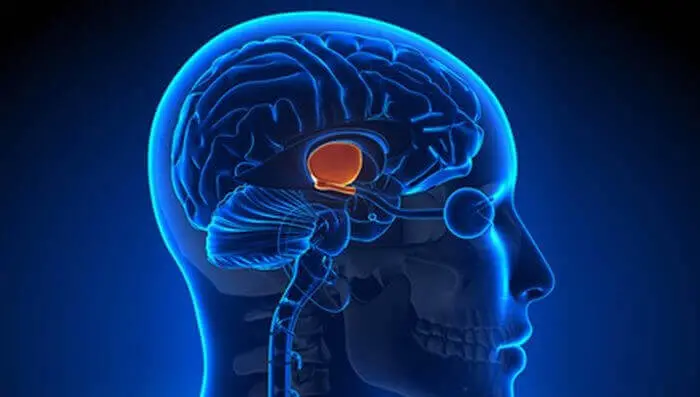

Дословный перевод понятия «вегетососудистая дистония», или ВСД – это изменение тонуса сосудов ввиду нарушения их регуляции вегетативным отделом нервной системы. Вегетативный отдел нервной системы имеет непосредственное отношение к головному мозгу, в частности – к гипоталамусу. Это небольшая, но очень важная область мозга. Гипоталамус — одна из наиболее древних частей головного мозга, которая обеспечивает практически все приспособительные реакции организма. В первую очередь гипоталамус контролирует функцию сердечнососудистой системы, в частности – поддерживает тонус сосудов.

Механизм стрессовой реакции, равно как и механизмы выхода из стресса заложены в работе головного мозга. Центром такой регуляции, напомним, есть гипоталамус.

Немного о гипоталамусе и его роли в ВСД

За сосудистые ответы организма на разные жизненные ситуации отвечает центральный регулятор вегетативных (приспособительных) реакций– гипоталамус. Это центральный регулятор сосудистых реакций в виде спазма и расслабления сосудов кожи, мышц, кишечника, почек … и даже сосудов самого мозга.

Cбой в работе гипоталамуса (центральный регулятор сосудистых реакций) приводит к развитию вегетососудистой дистонии (ВСД).